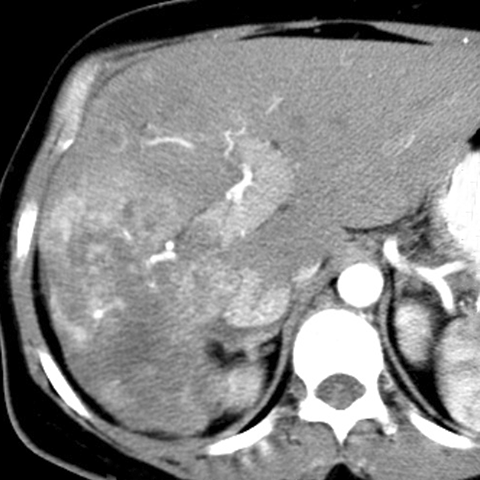

67 year-old male presents with weight loss, fatigue and jaundice. [2 of 2]